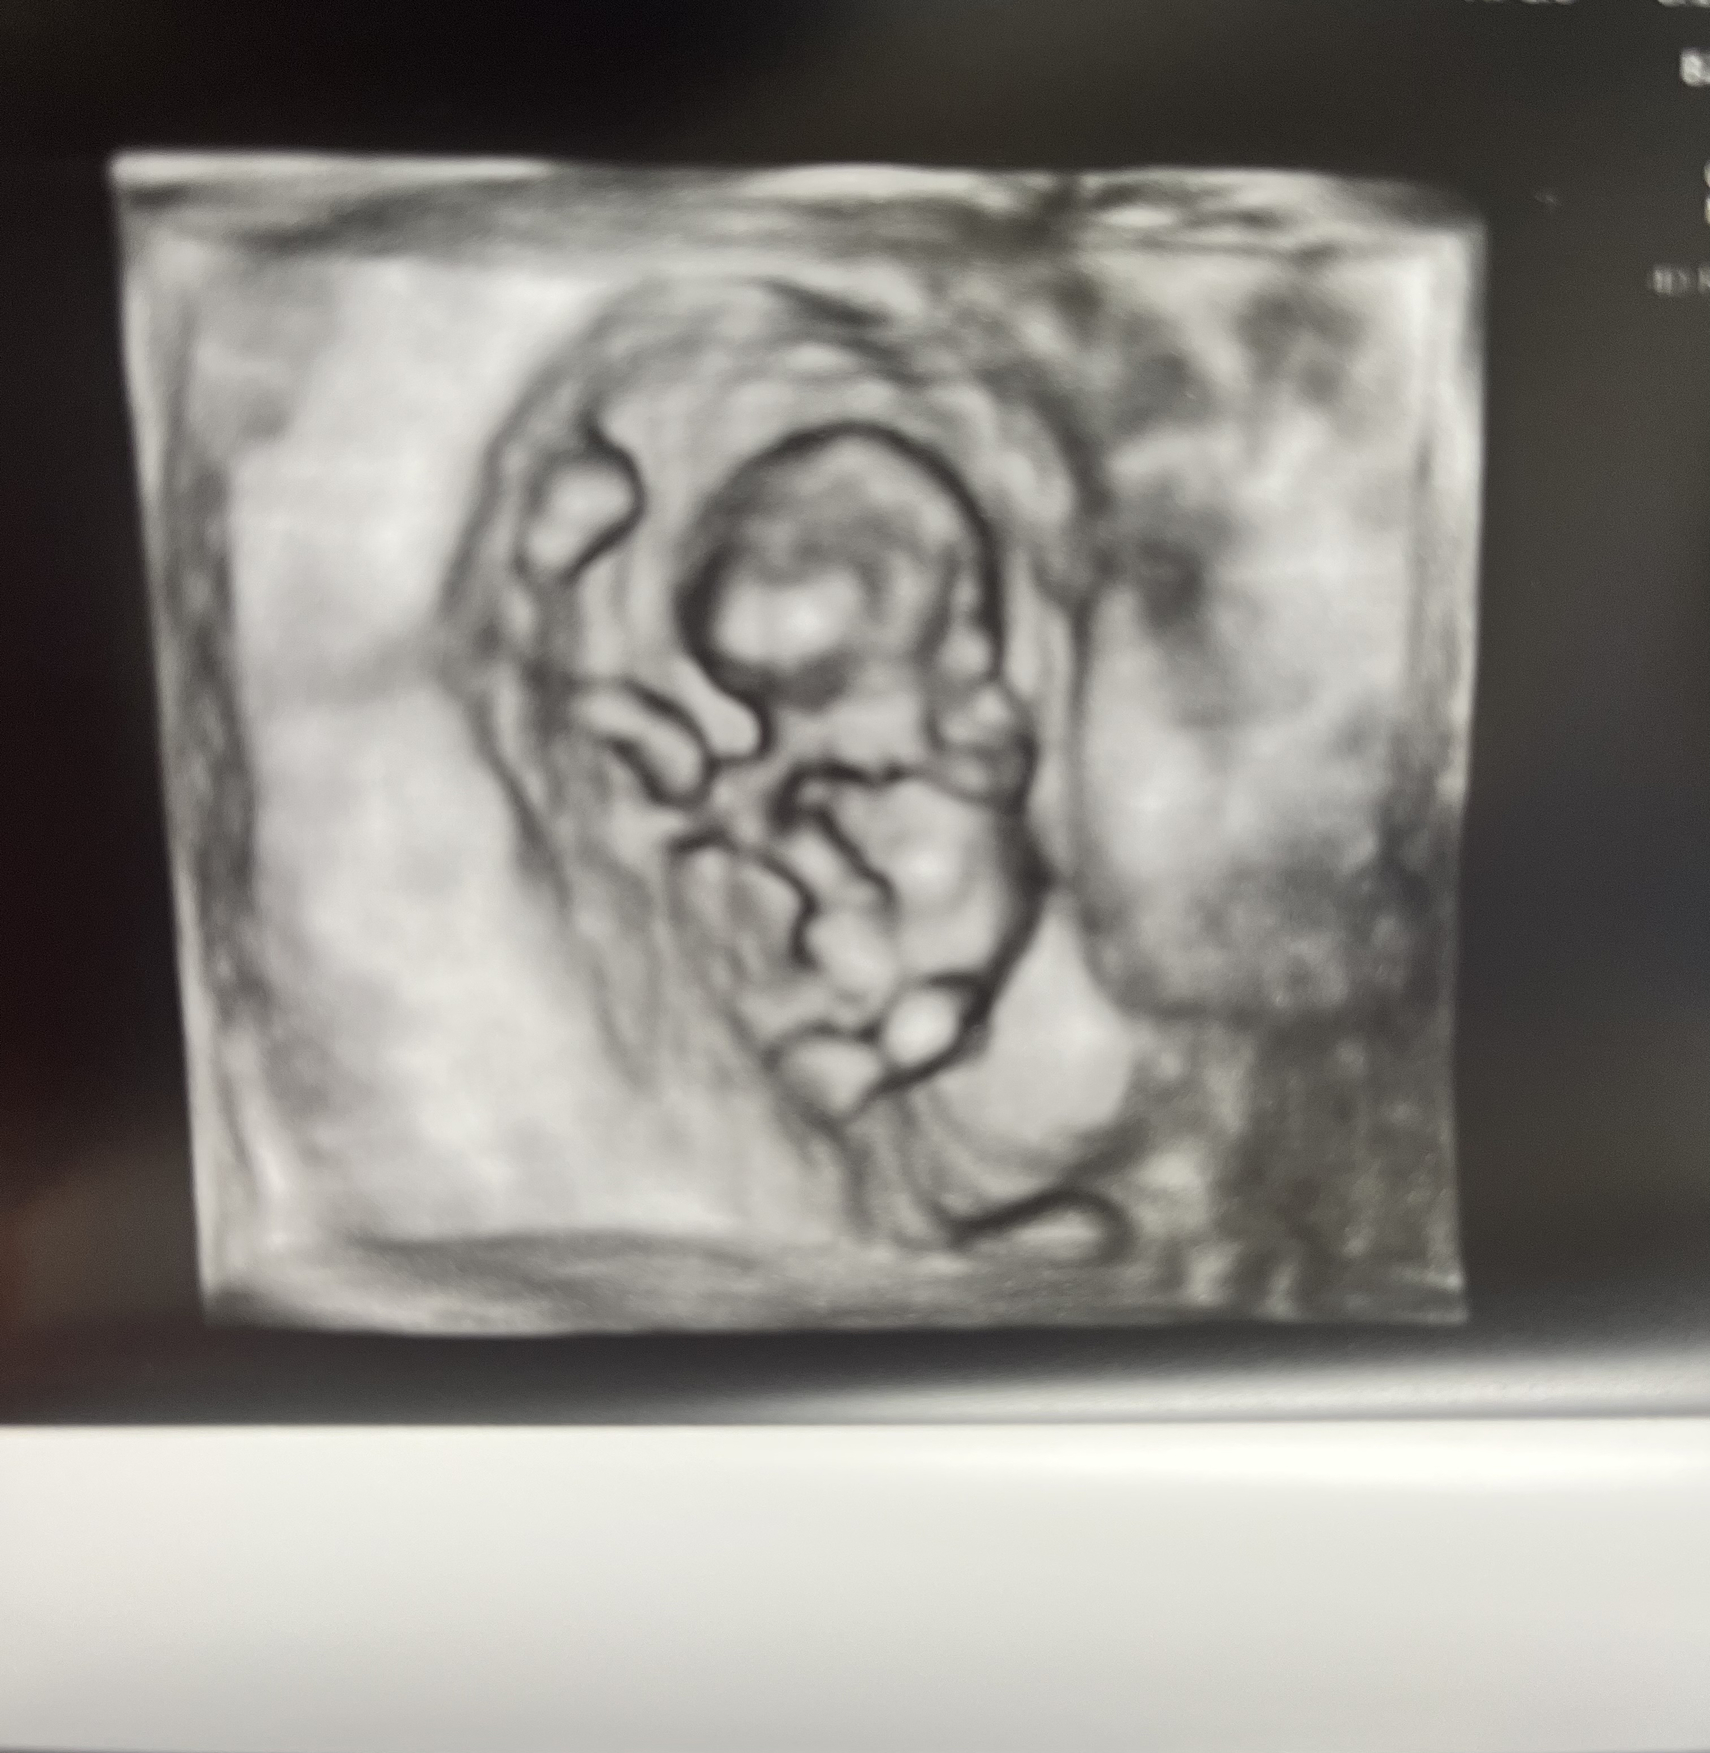

It's really real. They adjusted my due date by 1 day so I guess I'm now 9 weeks on the dot and due 11/2. Strong heartbeat at 178 bpm. Had a fun appointment explaining to all the new doctors that this is my 4th total pregnancy (2 viable, 1 mc) and we already have 4 kids. It took them a minute. 🤣

Crazy to see how big my uterus is in comparison lol.